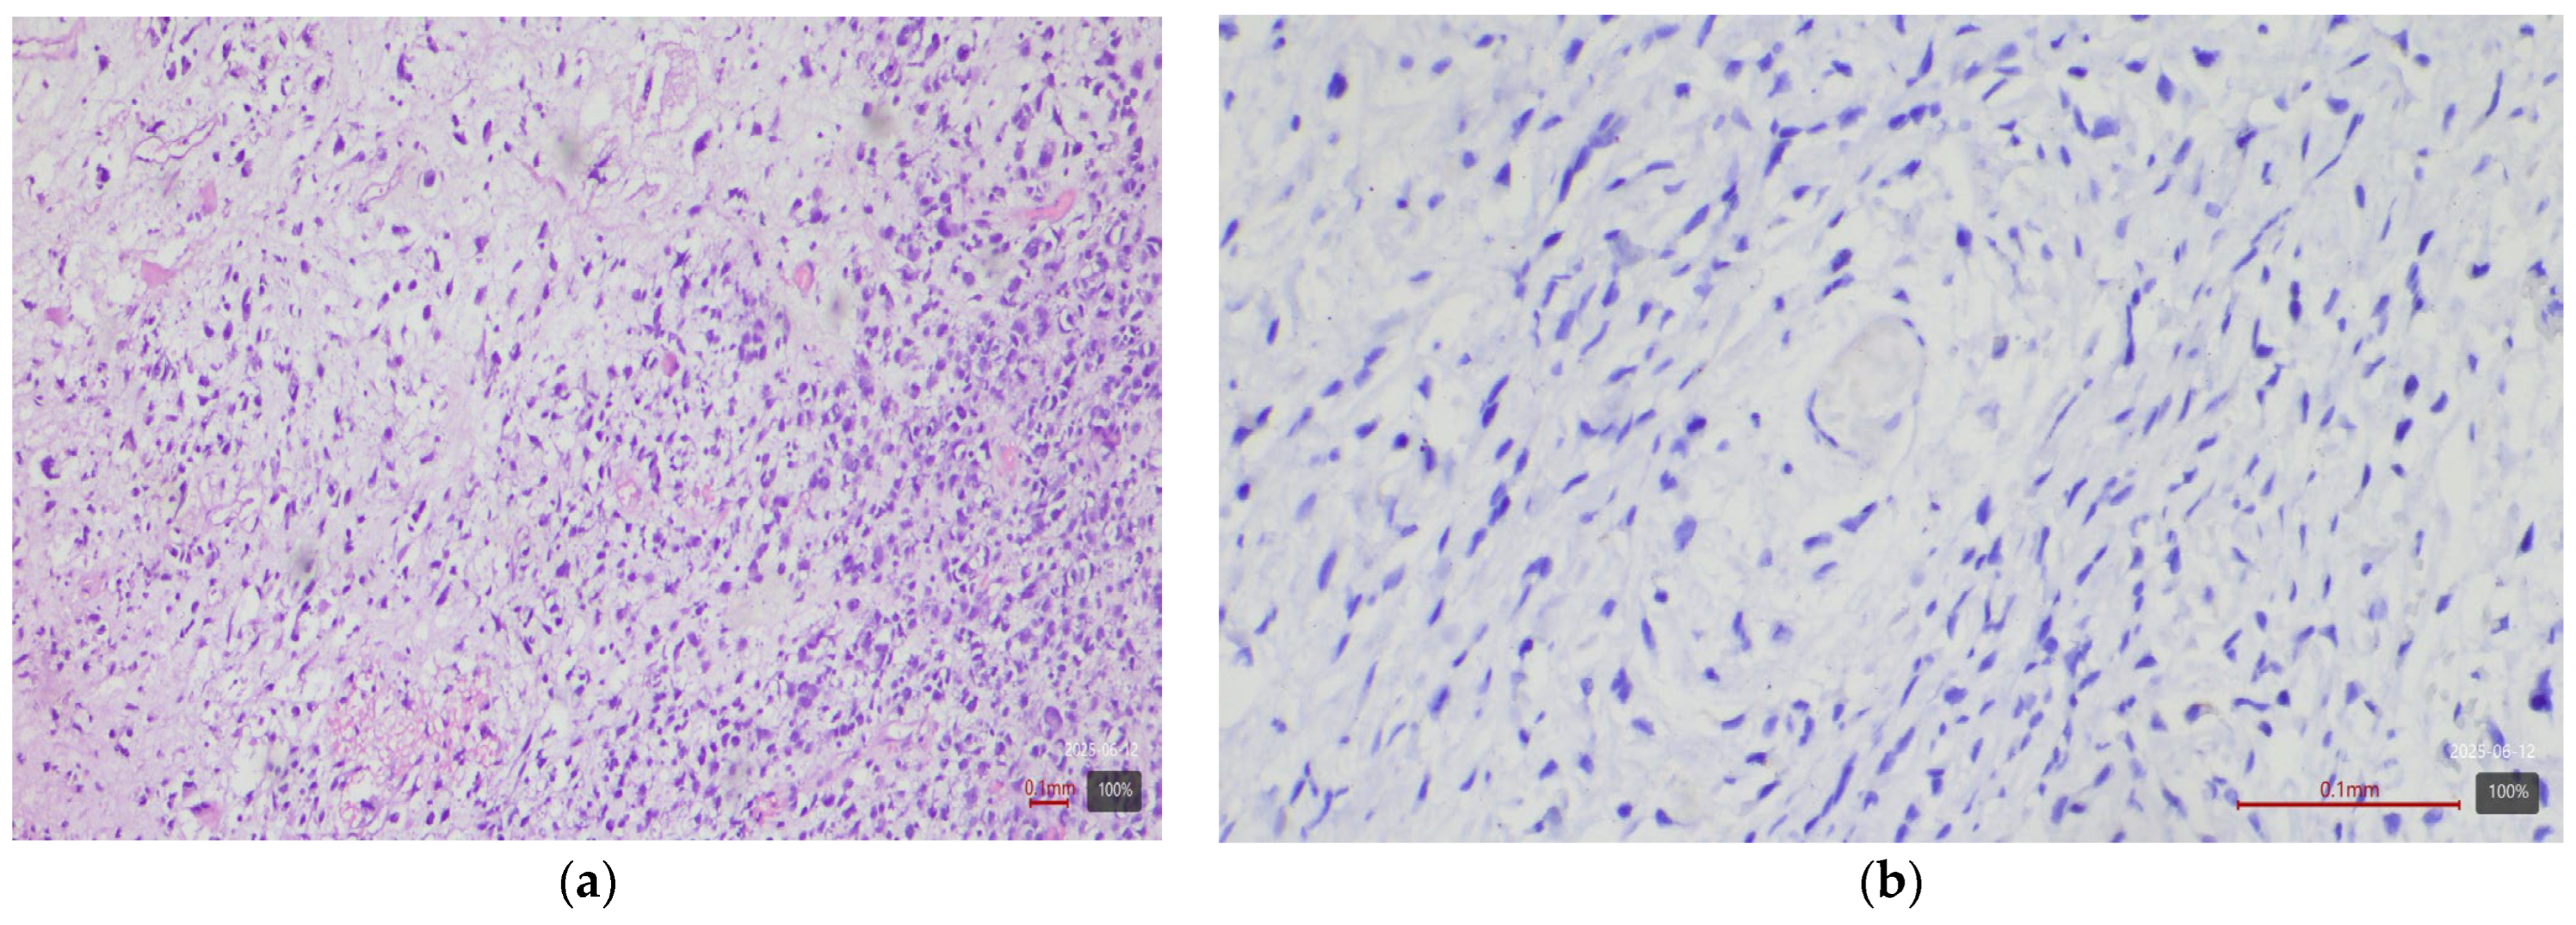

| Histological Subtype | Number of Cases (n) | HER2 3+ | HER2 2+ |

|---|---|---|---|

| Urothelial carcinoma (NOS) | 4 | 0% | 25% |

| Papillary urothelial carcinoma | 27 | 44% | 26% |

| Micropapillary subtype | 4 | 75% | 25% |

| Plasmacytoid subtype | 3 | 33% | 33% |

| UC with squamous differentiation | 17 | 0% | 0% |

| UC with glandular differentiation | 3 | 0% | 33% |

| Nested subtype | 2 | 50% | 0% |

| Sarcomatoid subtype | 5 | 0% | 0% |

| Small cell carcinoma | 5 | 0% | 0% |